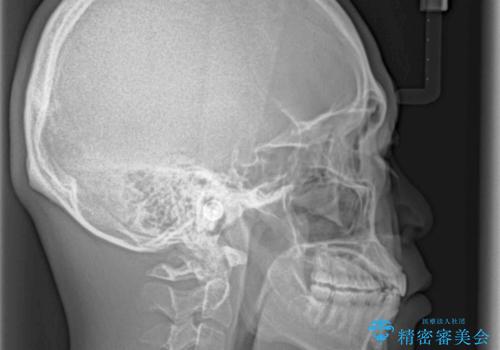

- 上下前歯のデコボコと下の前歯が隠れるほどの深い咬み合わせを気にして来院された患者様です。

インビザラインによる上下歯列の拡大と、IPR(歯と歯の間を削る)にるスペースの獲得により、口元のデコボコとディープバイトを改善することとしました。

デコボコがなくなったことで日頃の清掃が行いやすくなり、深い咬み合わせが改善したことで、食いしばりによる顎の負担も軽減されました。